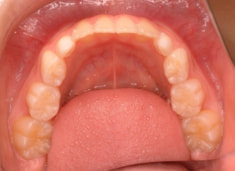

治療前